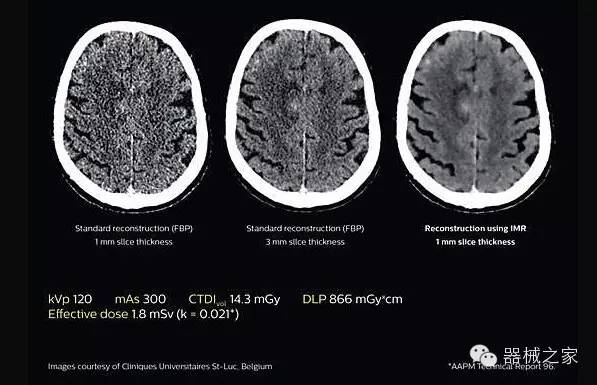

應(yīng)用目前業(yè)界領(lǐng)先的新一代星光平臺(tái)iDose4 Premium及基于迭代基礎(chǔ)的O一MAR去除金屬偽影技術(shù),達(dá)成微量輻射下零偽影的高清晰成像;

2.腦部顯影